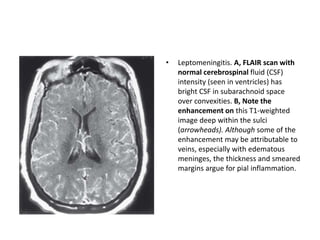

• Leptomeningitis. A, FLAIR scan with

normal cerebrospinal fluid (CSF)

intensity (seen in ventricles) has

bright CSF in subarachnoid space

over convexities. B, Note the

enhancement on this T1-weighted

image deep within the sulci

(arrowheads). Although some of the

enhancement may be attributable to

veins, especially with edematous

meninges, the thickness and smeared

margins argue for pial inflammation.